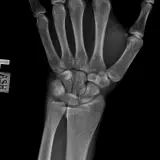

Over 2,100 interactive radiology cases, curated by radiologists for your level of training. Scroll, window, and view cases full screen — just like on PACS. Click linked findings in each writeup to jump straight to them on the image. Cases include sample reports, a focused discussion section, original illustrations, and videos.

Casos totalmente interactivos con las herramientas que esperaría de un PACS: scroll, ventana, zoom, pan, mediciones, ROI y modo de pantalla completa.

• Anotaciones enlazadas

Anotaciones extensas resaltan los hallazgos clave directamente sobre los casos. Haga clic en los hallazgos enlazados dentro de la descripción del caso para saltar a su ubicación exacta en el estudio.

Aprenda con eficiencia gracias a hallazgos de imagen anotados e ilustraciones